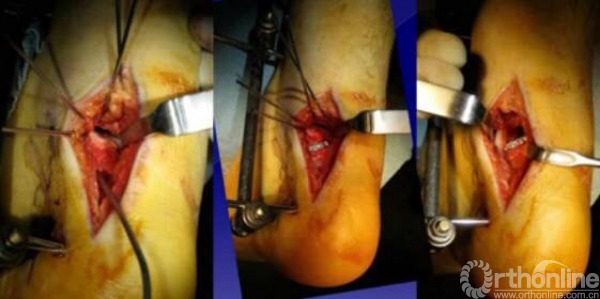

1.内侧入路

比较安全,注意大隐静脉和隐神经

骨折十分粉碎时可采用内踝截骨,事先可进行螺钉的拧入,类似鹰嘴截骨。

2.外侧入路

如果一侧钢板的位置不佳,则容易造成另外一侧的骨折裂开。所以最好的固定是一侧用钢板固定,另外一侧可采用螺钉进行加压,对于颈部的骨折,避免另外一侧开口。

3.后侧入路:对于特殊的后侧距骨骨折

两侧切口无法进行复位,可采用后侧入路进行复位以及固定。